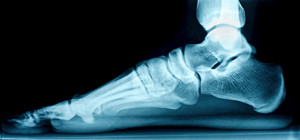

What Are Flexible Flat Feet?

The term “flexible flat feet” refers to one of the most common types of flat feet. People with this condition have no visible arches when they are standing, but do have visible arches when they aren’t. This condition usually begins in childhood and continues into the adult years, getting progressively worse over time. The tendons and ligaments of the arch may eventually stretch or tear, becoming inflamed and painful. The typical symptoms of flexible flat feet include pain in the heel, arch, or ankle, feet that roll inward when you walk, pain along the shin, and a general aching or tiredness in the feet or legs. There are a variety of treatment options available for this condition, such as orthotic devices, or activity and shoe modifications. For more information about flexible flat feet, please consult with a podiatrist.

What Are Flat Feet?

Flatfoot is a condition in which the arch of the foot is depressed and the sole of the foot is almost completely in contact with the ground. About 20-30% of the population generally has flat feet because their arches never formed during growth.